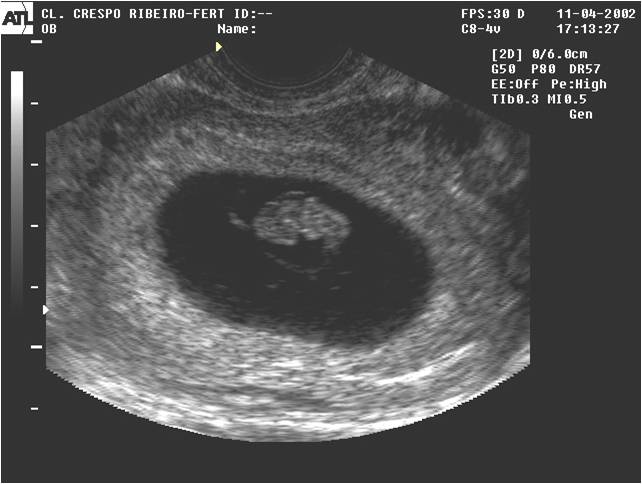

O líquido amniótico é aquele que se encontra dentro da bolsa onde está o bebê. O líquido amniótico envolve o bebê durante todo o seu desenvolvimento, dentro do saco amniótico, também conhecido como bolsa das águas.

Para medir a quantidade de líquido, é preciso fazer um ultra-som. Seu médico vai solicitar um se desconfiar de que a quantidade de líquido está abaixo da ideal. Veja alguns sinais de que isso pode estar ocorrendo:

Com a ultra-sonografia, dá para medir os bolsões de líquido em vários pontos do útero (o espaço entre o bebê e a parede uterina), e o especialista faz um cálculo que resulta no índice de líquido amniótico (ILA). No terceiro trimestre, o ILA deve estar entre 5 cm e 25 cm. Um índice abaixo de 7 cm é considerado sinal de alerta, e com menos de 5 cm pode fazer com que os médicos prefiram adiantar o parto.